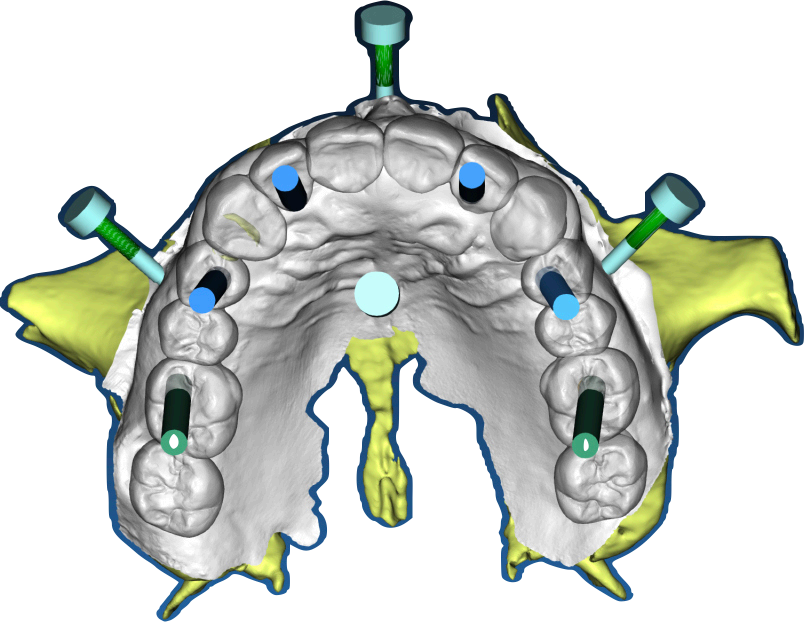

Group 2: Surgical Procedure Fig. 2.1: 3D model of the stackable surgical guide with fxation bar. Fig. 2.2: Occlusal view of the osteotomy guide in use during surgery. Fig. 2.3: Frontal intraoral view post-implant placement with MUAs attached. Fig. 2.4: Occlusal view of coded scan body captured by Shining3D Elite photogrammetry.

The surgical procedure was performed under local anesthesia in a single session. The residual roots at 13 and 21, along with the fractured teeth at 22 and 13, were extracted with minimal trauma to preserve the surrounding bone and soft tissue. The stackable guide was secured intraorally using the fxation bar anchored to the maxilla, providing a stable reference for implant placement (Fig. 2.2). Osteotomies were prepared at the planned sites (16, 14, 12, 22, 24, 26) using the guide’s drilling sleeves, ensuring accuracy in depth and angulation. Six implants were inserted, and multi-unit abutments (MUAs) were immediately placed to facilitate prosthetic connection (Fig. 2.3).

Following implant placement, intraoral photogrammetry was performed using the Shining3D Elite scanner. Scan markers were attached to the MUAs, and their positions were captured with high precision (Fig. 2.4, 3.4). Multiple scans were acquired, including the maxillary arch (Fig. 3.1), the fxation bar from the stackable guide (Fig. 3.2), the MUAs (Fig. 3.3), and the surrounding soft tissues (Fig. 3.5). The photogrammetry data was merged with conventional intraoral scans, using the fxation bar as a fduciary to align all datasets accurately (Fig. 3.7). A heat map generated in the software confrmed the precision of this alignment, with minimal discrepancies across the arch (Fig. 3.7). The scan markers were then converted to implant-specifc analogs compatible with the chosen implant system (Fig. 3.6).

Group 3: Digital Scanning Fig. 3.1: Full maxillary scan prior to merging. Fig. 3.2: Scan of the fxation bar from the stackable guide as a fduciary reference. Fig. 3.3: Scan showing MUAs in position. Fig. 3.4: Photogrammetry scan markers captured intraorally. Fig. 3.5: Composite scan integrating photogrammetry markers with soft tissue data. Fig. 3.6: Conversion of scan markers to implantspecifc analogs. Fig. 3.7: Heat map illustrating scan alignment accuracy post-merging. Fig. 3.8: Design of the provisional prosthesis with screw channel holes.